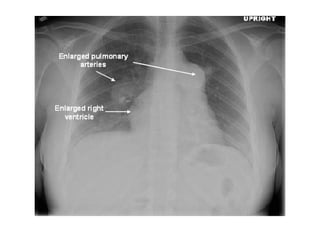

c) Radiographic Features :

-Increased diameter of the pulmonary arterial trunk

(>2.9 cm), the main pulmonary arteries and their

segments and in more advanced cases , the

right heart chambers and azygos-hemiazygos

venous system

Yellow arrow shows enlarged right main pulmonary artery ,

red arrow shows the enlarged left pulmonary artery